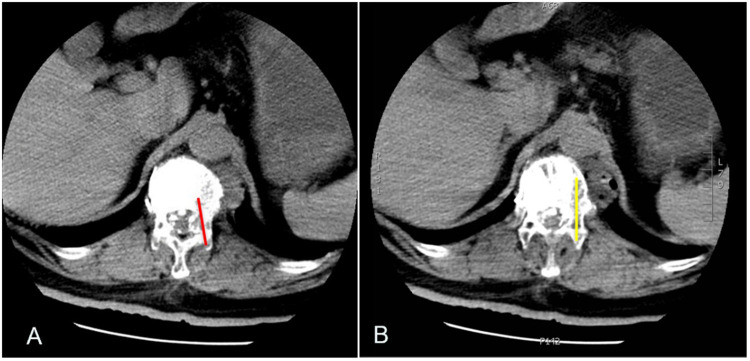

Case report: We designed a prospective cohort study to evaluate the outcomes following of percutaneous vertebroplasty using GeneX in patients with osteoporotic vertebral compression fractures. Vertebroplasty was performed at seven vertebrae in the first seven patients. Overall, there were four leaks in four (57%) of the seven patients. Asymptomatic leak of the GeneX material into the intradiscal and paravertebral structures at the treated vertebral level was observed in three patients (43%). However, the material leaked into the intradural and epidural space in the seventh patient (14%), causing severe neurological deficits. Primary diagnosis was bone cement implantation syndrome. The patient's neurological status improved gradually during the month after surgery. She was able to resume her activities of daily living and had regained her urinary function by 3 months after surgery.